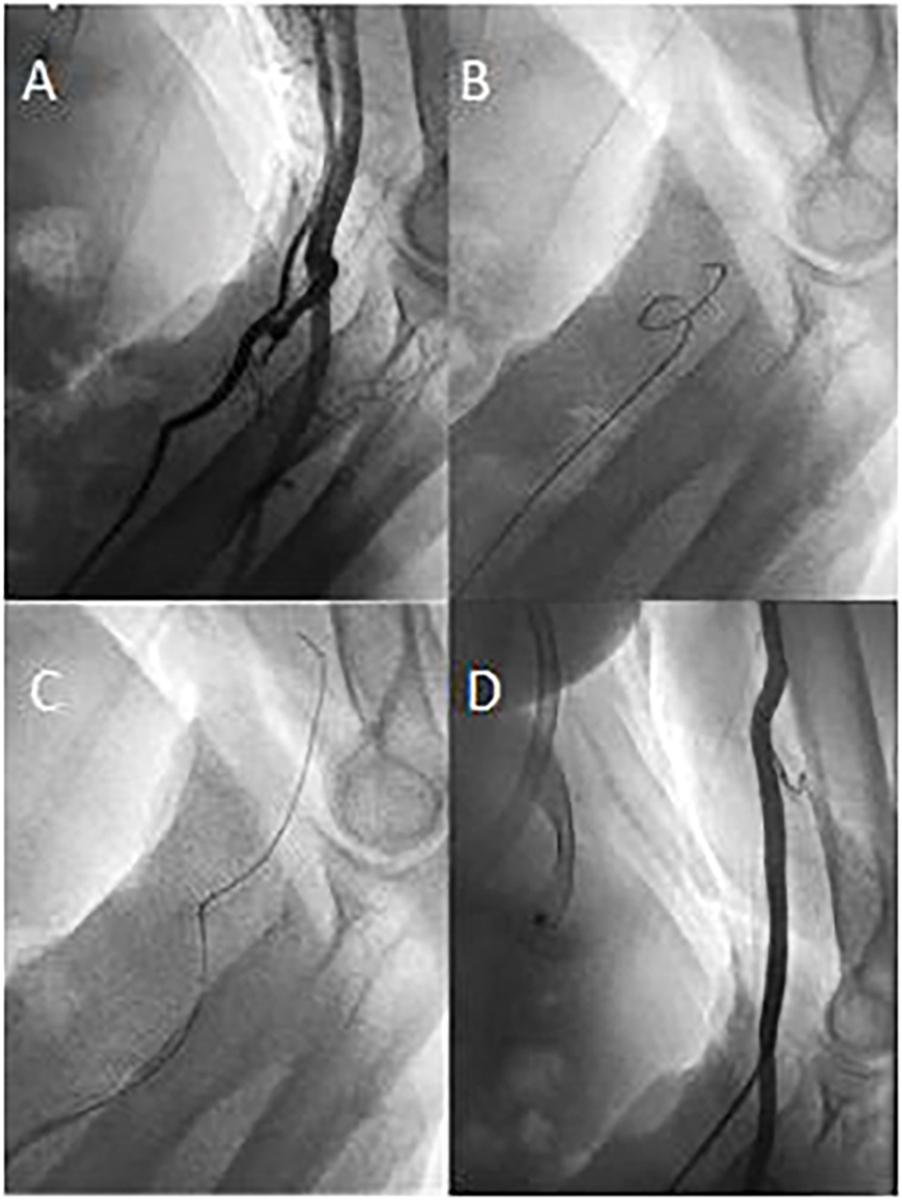

There is a consensus, that Transradial-Access (TRA) for coronary procedures should be preferred over Transfemoral-Access (TFA). Previously, Forearm-Artery-Angiography (FA) was mainly performed when difficulties during the advancement of the guidewire/-catheter were encountered. We explored the implication of a Standardized Forearm-Angiography (SFA) on procedural success rates of TRA under real-world conditions.

In a single-center study, an all-comers-cohort of 1191 consecutive cases during 1/2020-12/2020 were assessed retrospectively. Primary TFA rates, crossover to TFA, reasons for Forearm-Artery-Access (FAA) failure, the prevalence of kinking at the level of the forearm and the occurrence of vascular complications were analyzed. Major forearm side branches including the common interosseus artery were assessed via SFA.

In 1191 consecutive procedures, primary FAA access was attempted in 97.9% of cases. Crossover to TFA after a primary or secondary FAA attempt was necessary in 2.8%. Severe kinking was the most frequent cause of FAA failure and occurred in 3.0% of attempts. A second or third FAA attempt to avoid TFA was successful in 81%. Severe kinking at the level of the forearm was reported in 1.8% of procedures.

This is the first study to provide detailed success rates of a primary FAA strategy combined with a Standardized-Forearm-Angiography (SFA) in an all-comers-cohort. While severe kinking proved to be a rare but relevant challenge for FAA success, the prevalence of arterial spasm was marginal. Multiple attempts of FAA to avoid TFA might be safe possibly due to collateral blood supply by the common interosseus artery.